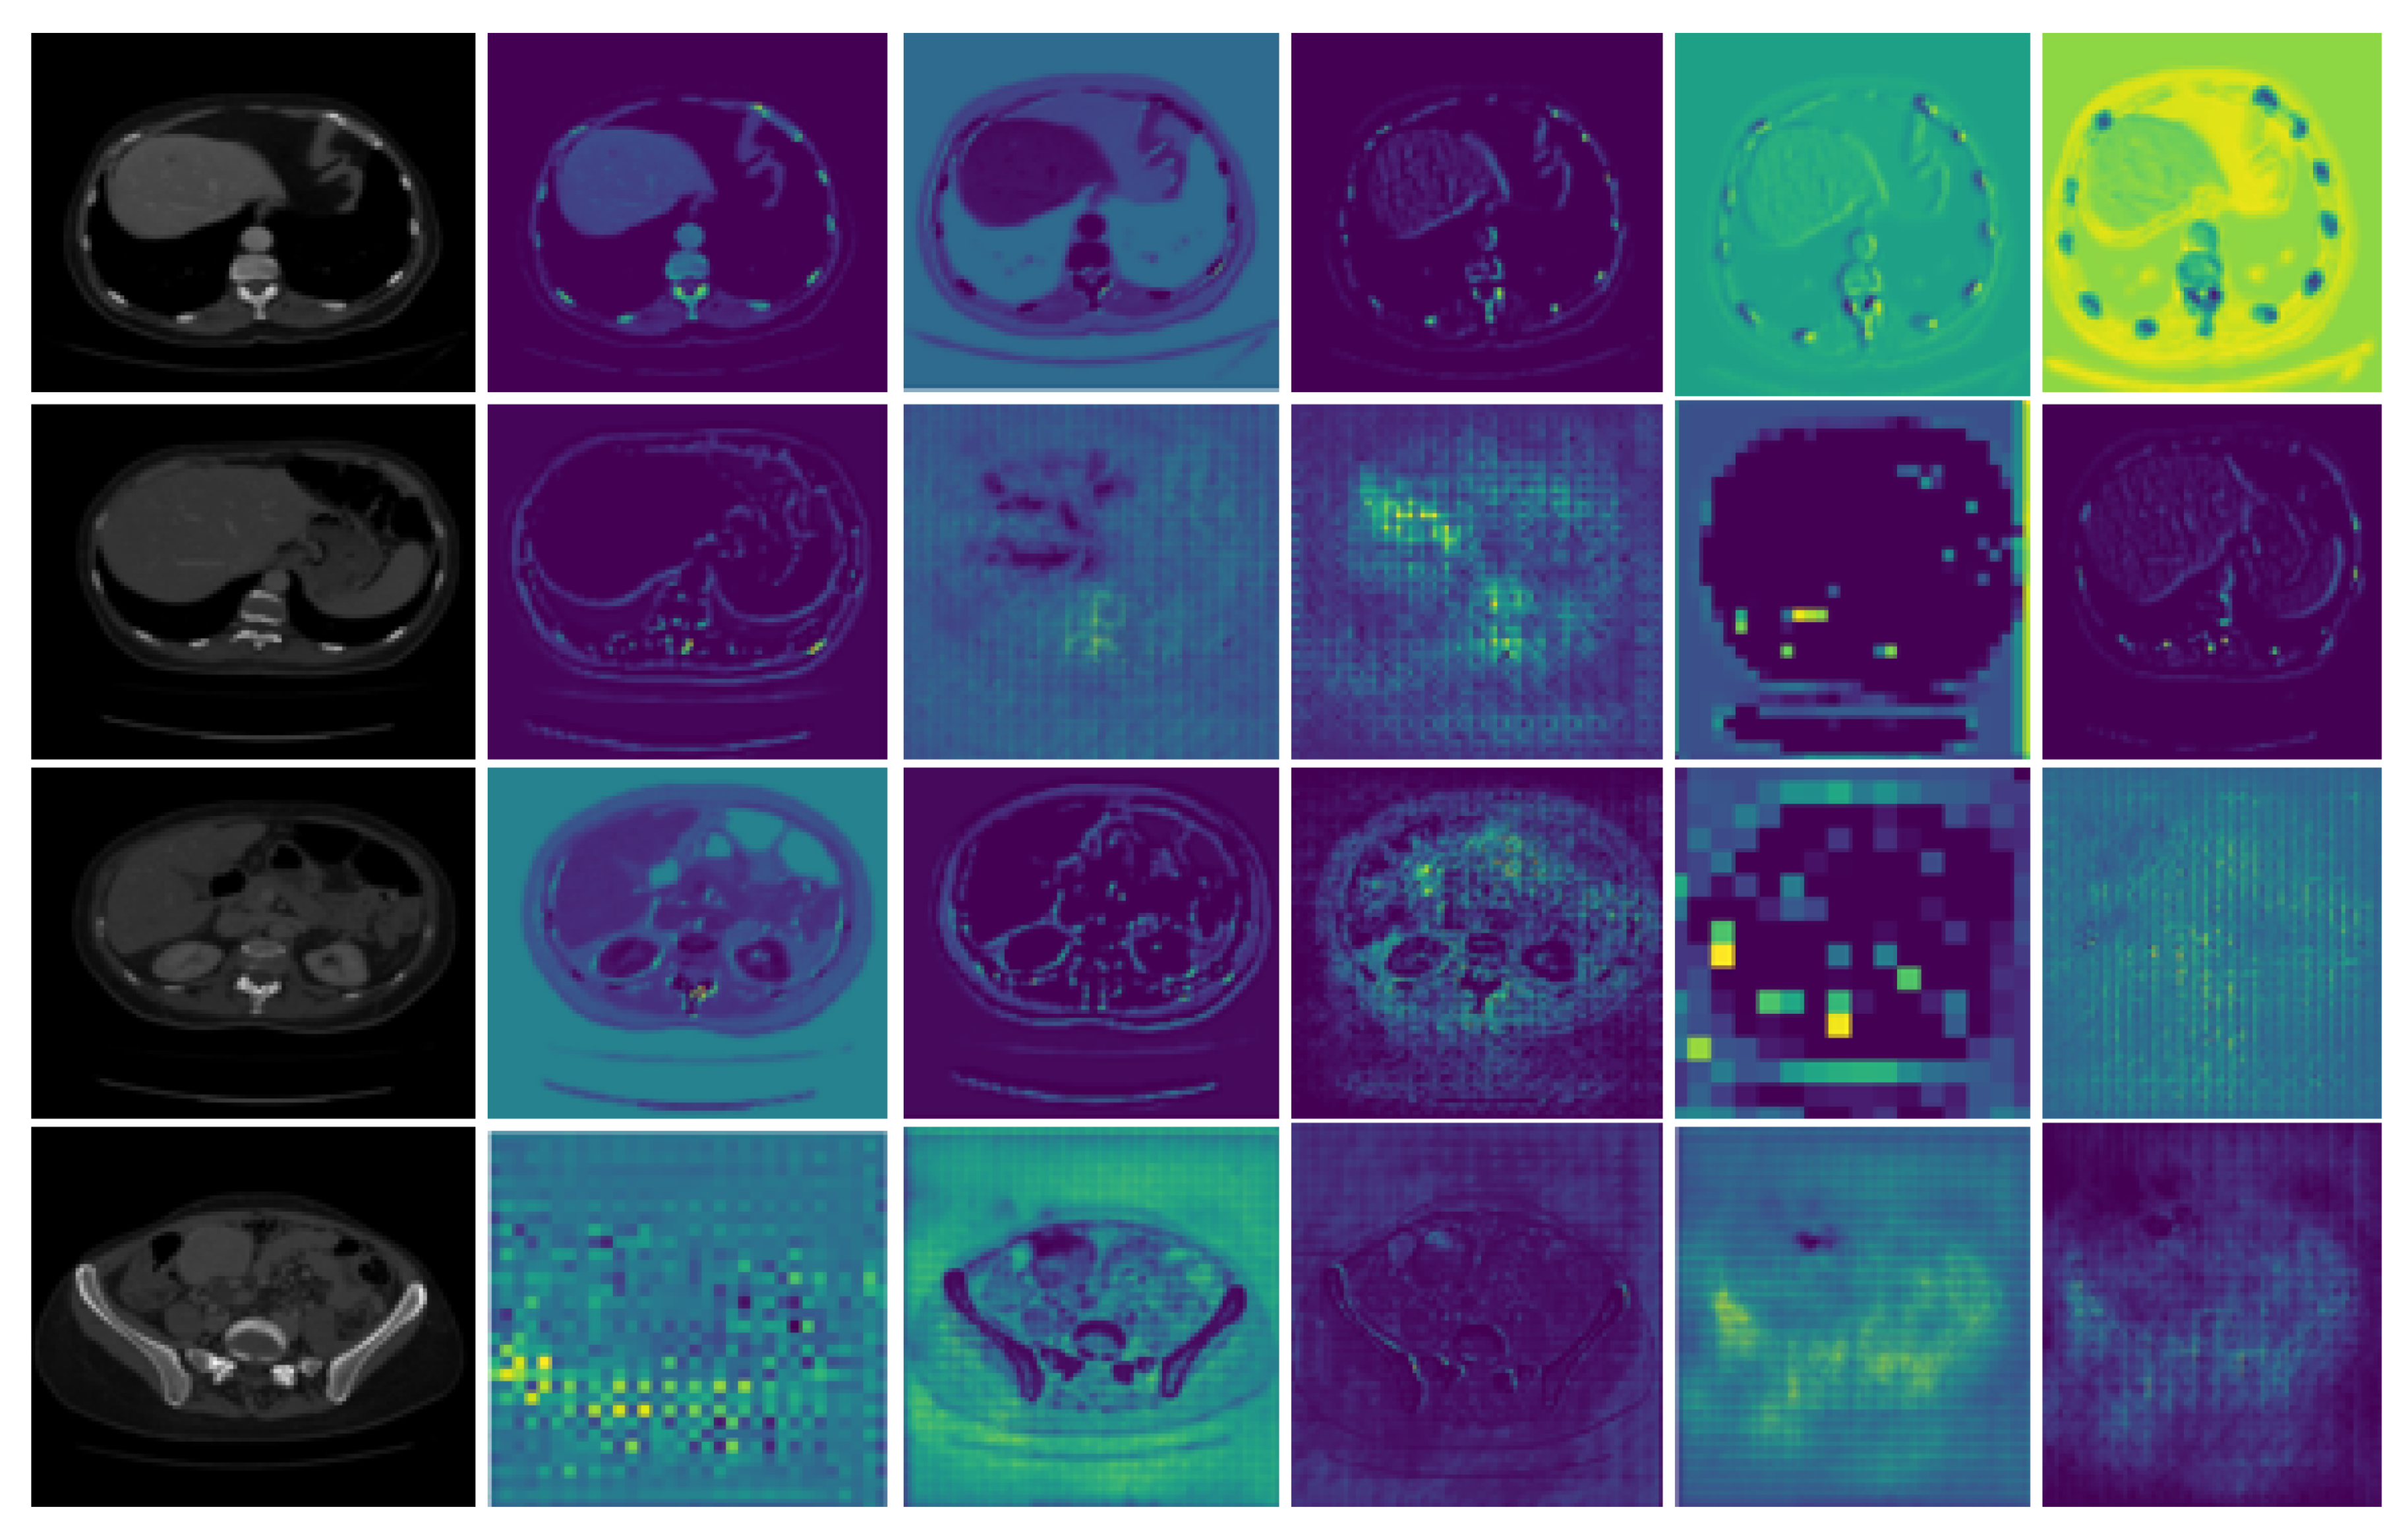

Moreover, during training, the input image of the CT scan is passed through different layers of the model, which includes convolution layers and pooling layers. The output of each layer takes the form of activation maps. The visualization of those activation feature maps of some intermediate layers of our proposed model is also shown in Figure 5. These visualizations show how the model depicts the contextual information of the image layer by layer.

Figure 5.

Visualization of the activation maps of an intermediate layer.